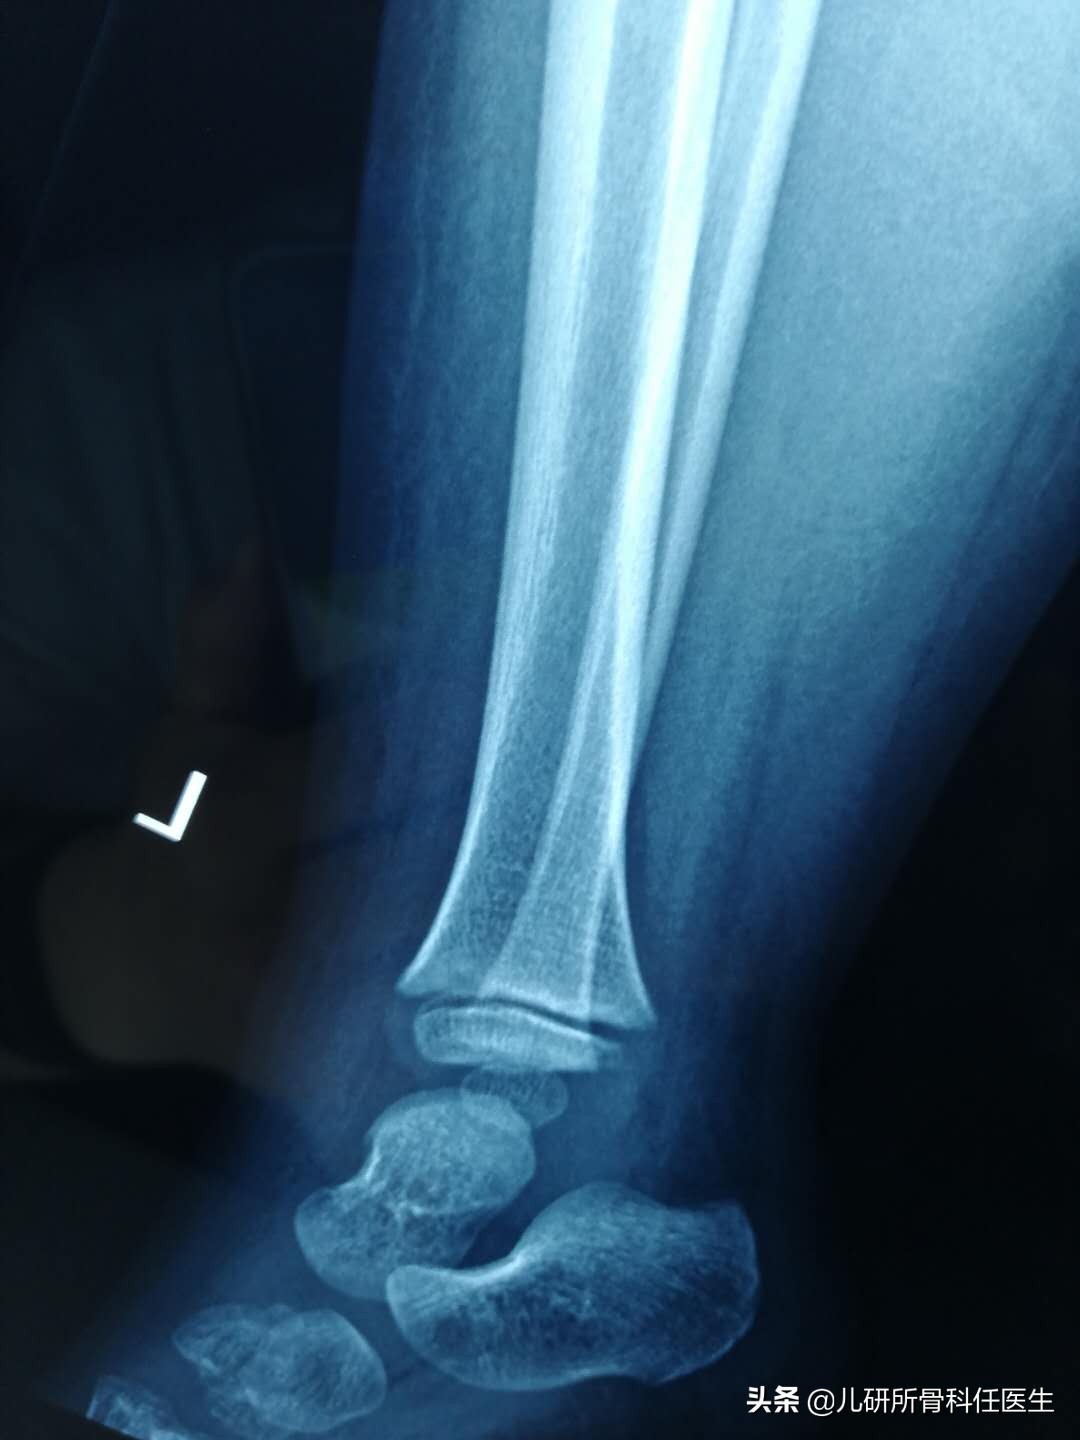

这种情况,根据我的经验,蚊虫叮咬的可能性很大,但是问孩子妈妈说没记得有蚊虫咬过(估计蚊子饱餐一顿后没有跟妈妈那里买单)。为了防止误诊和漏诊,任医生还是给孩子做了两项检查,一是拍了踝关节的正侧位x线片,同时查了血常规和C反应蛋白(儿研所的这两项检查只需要查指尖血就可以),主要是要排除骨损伤和软组织感染两种情况。

经过漫长的等待,结果出来了,X线提示未见明显骨损伤。